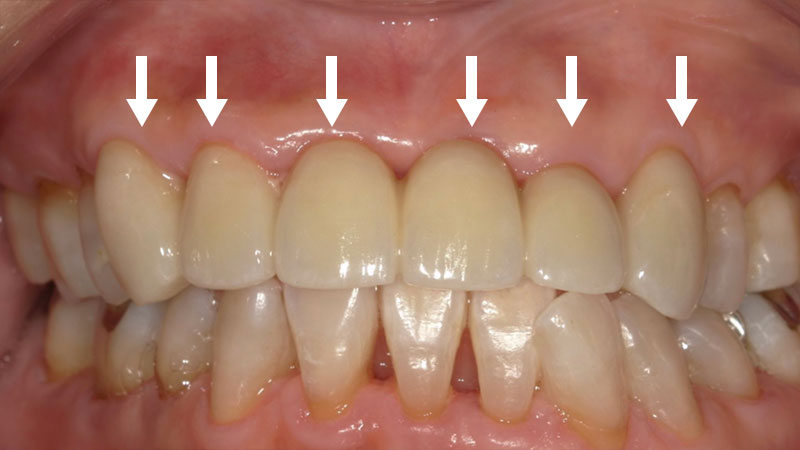

オフィスホワイトニング症例

オフィスホワイトニング症例をご紹介します。

今回させていただいたオフィスホワイトニングはプラチナコースになります。

通常のオフィスホワイトニングの3回コースをお得にできます。

また、シミ止めと歯を強くするコーティングもさせていただきます。

| 患者様 | 50代男性 |

|---|---|

| 主訴 | 歯を白くしたい |

| 治療費 | 総額44,000円(税込) ※当時の価格より現在は費用が上がっております |

| 治療期間 | オフィスホワイトニング3回 約1ヶ月 |